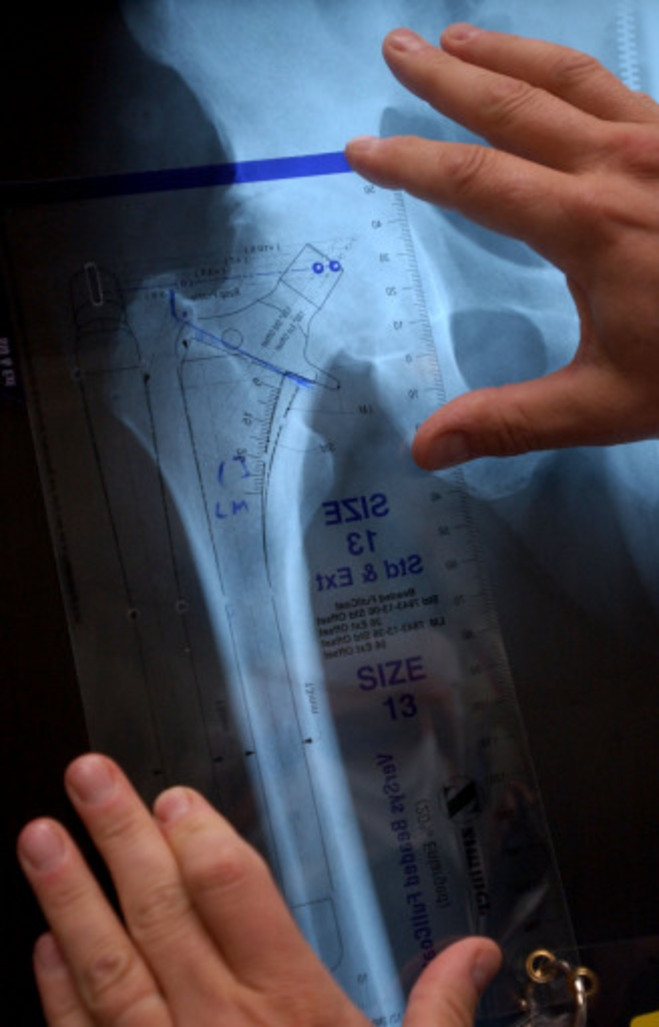

What Brand Of Hip Replacement Is Being Recalled . From 2002 to 2013, consumer's union. in june 2021, exactech recalled some gxl liners for novation, acumatch, and mcs hip replacement. Remove from inventory, all synovo total. the fda is getting the word out regarding a recall effort from zimmer biomet related to its discontinued cpt hip. the fda reminded healthcare providers and patients on thursday that several exactech joint replacement. do not purchase or implant the currently available synovo total hip system. irby is one of more than 1,100 patients suing exactech after it began recalling artificial knees, hips, and ankles,. causes for hip replacement recalls include design flaws, early implant failure and migration issues.